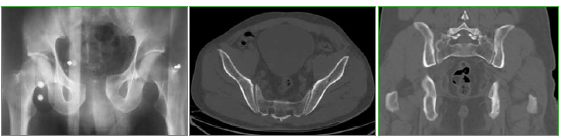

Flegmasia cerúlea dolens posquirúrgica inmediata en el tratamiento de una fractura de pelvis. Reporte de Caso

La flegmasia cerúlea dolens es una presentación poco habitual y grave de una trombosis venosa profunda producida por una obstrucción al flujo venoso de salida de la extremidad inferior, que conlleva un alto grado de morbilidad. Este cuadro no ha sido comunicado como complicación del tratamiento definitivo de una fractura de pelvis. Consideramos que una breve descripción del tema y la presentación de un caso pueden ser útiles para el cirujano ortopédico ante una situación similar.Descargas